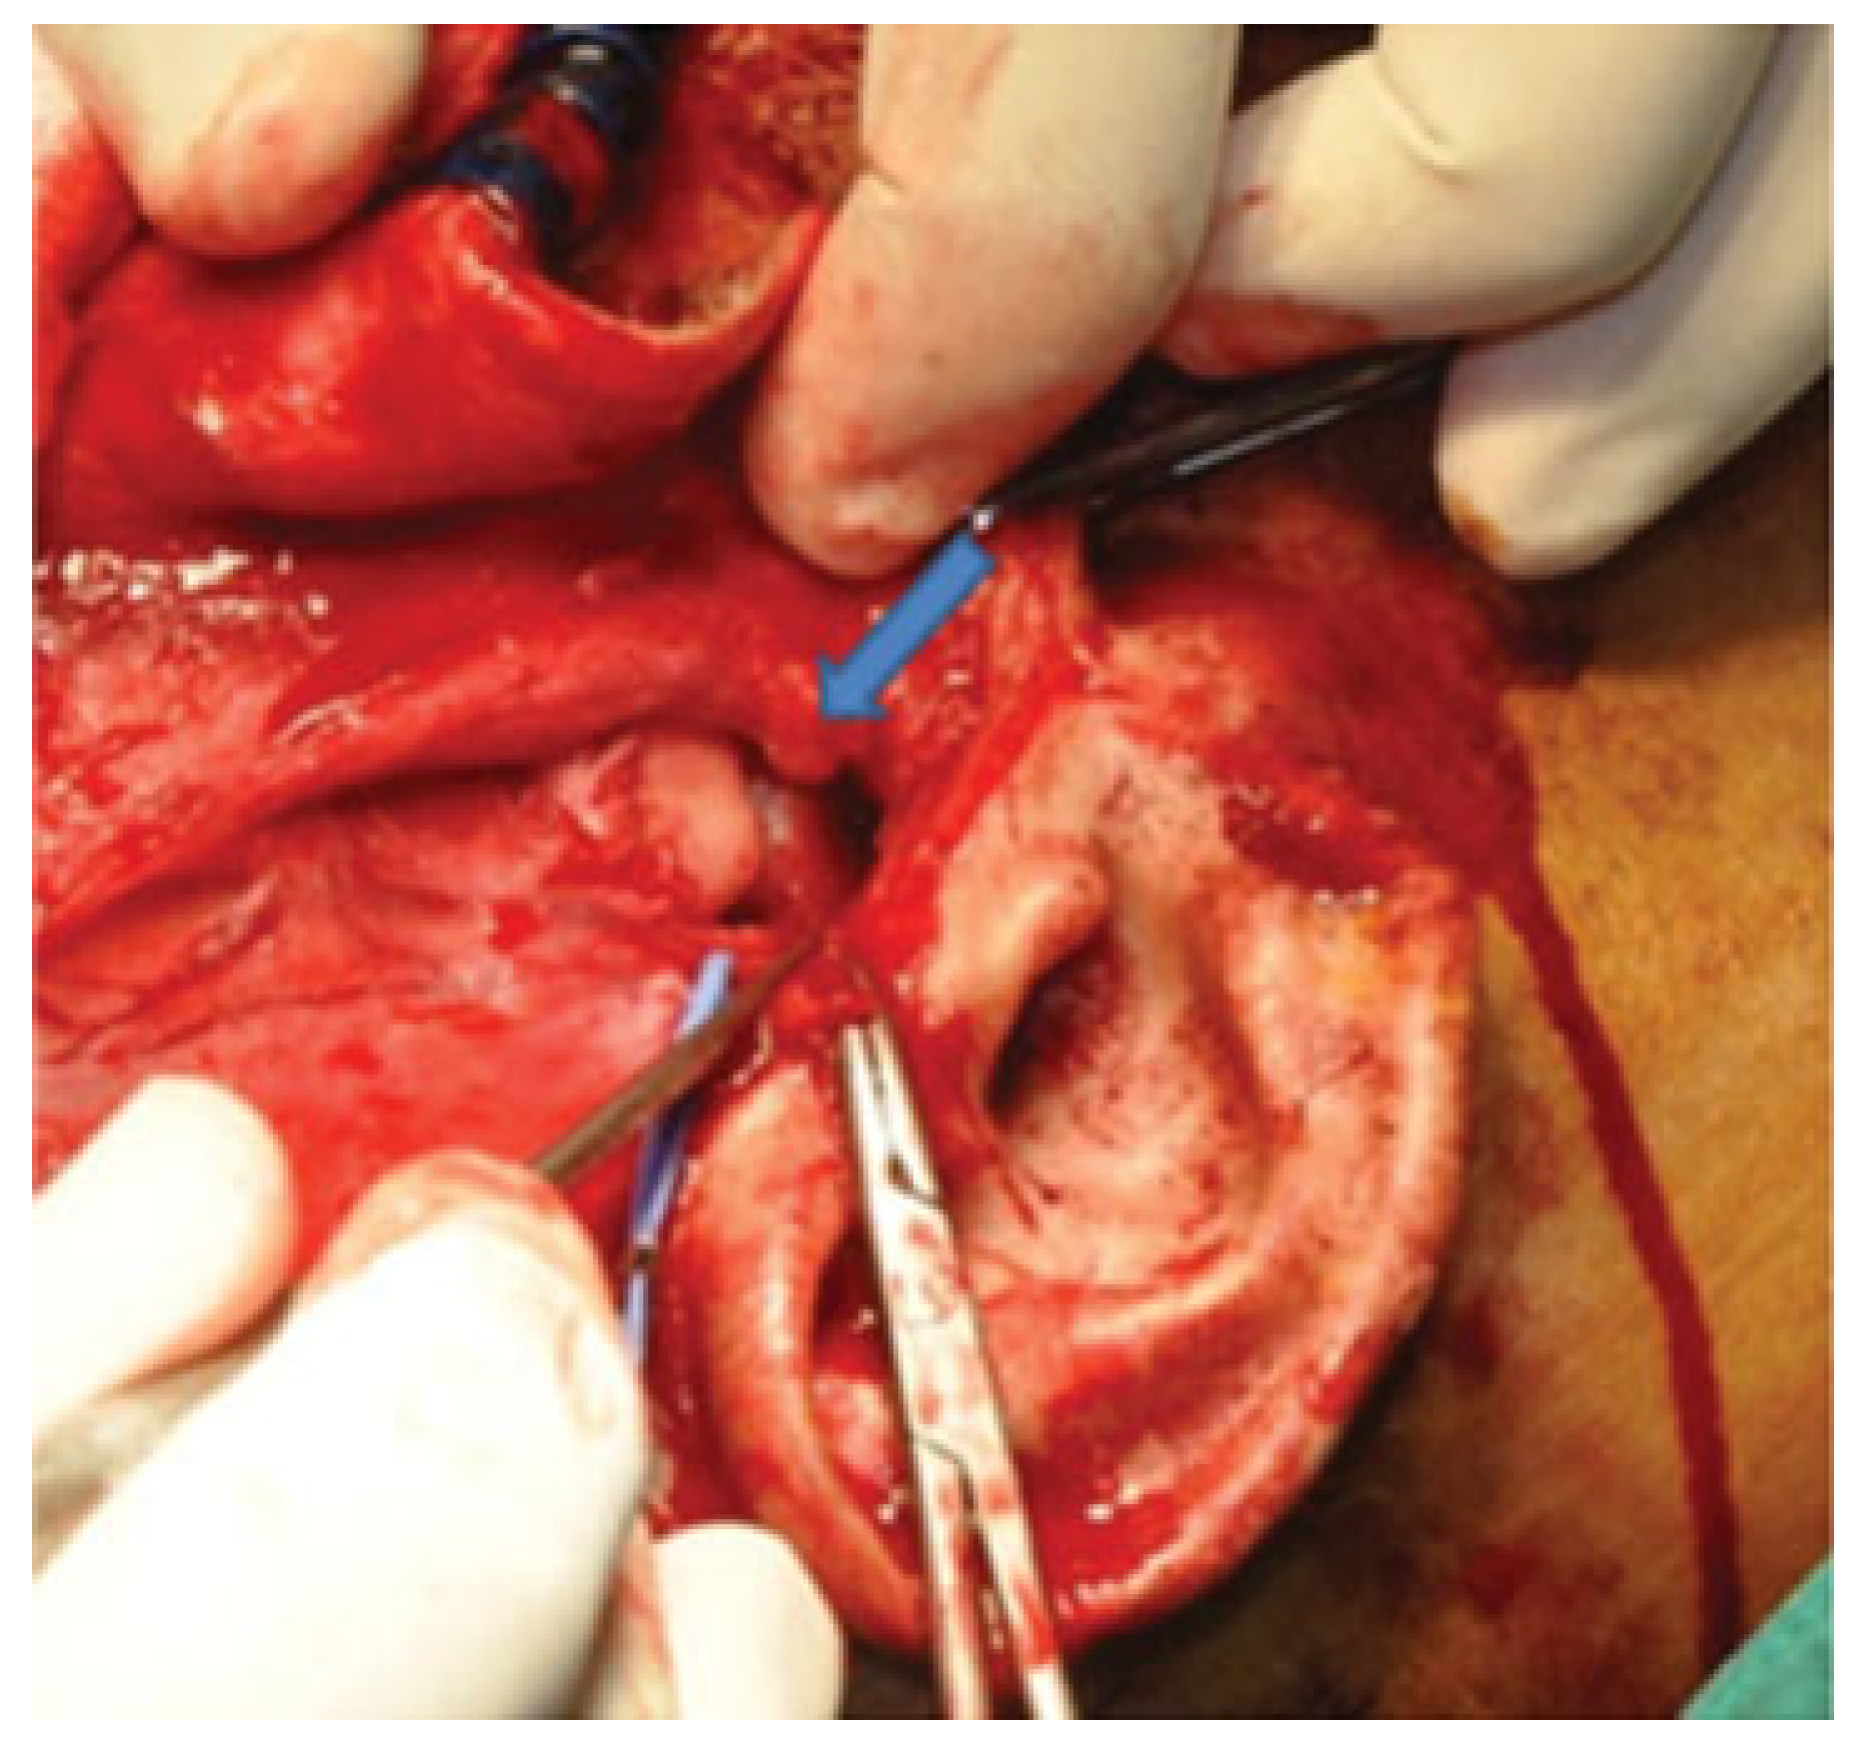

The glenoid fossae, articular eminences, and both dislocated mandibular condyles were fully exposed. Wasting of the temporalis muscle was noted. It became clear at this point that initial manipulation of the mandible to relocate the condylar heads into glenoid fossae was unsuccessful due to the presence of thick fibrous tissues around the TMJ capsules ([

Figure 3]). These fibrous tissues were then released and both TMJ capsules were cut. Rowe’s elevator was used to torque the mandibular condyles back into glenoid fossae. However, difficulty was encountered on the left side; thus, left eminectomy was decided ([

Figure 3.

Unsuccessful repositioning of condyle into glenoid fossae. Right condyle was seen just below the right articular eminence after manual reduction (arrow).

Figure 3.

Unsuccessful repositioning of condyle into glenoid fossae. Right condyle was seen just below the right articular eminence after manual reduction (arrow).